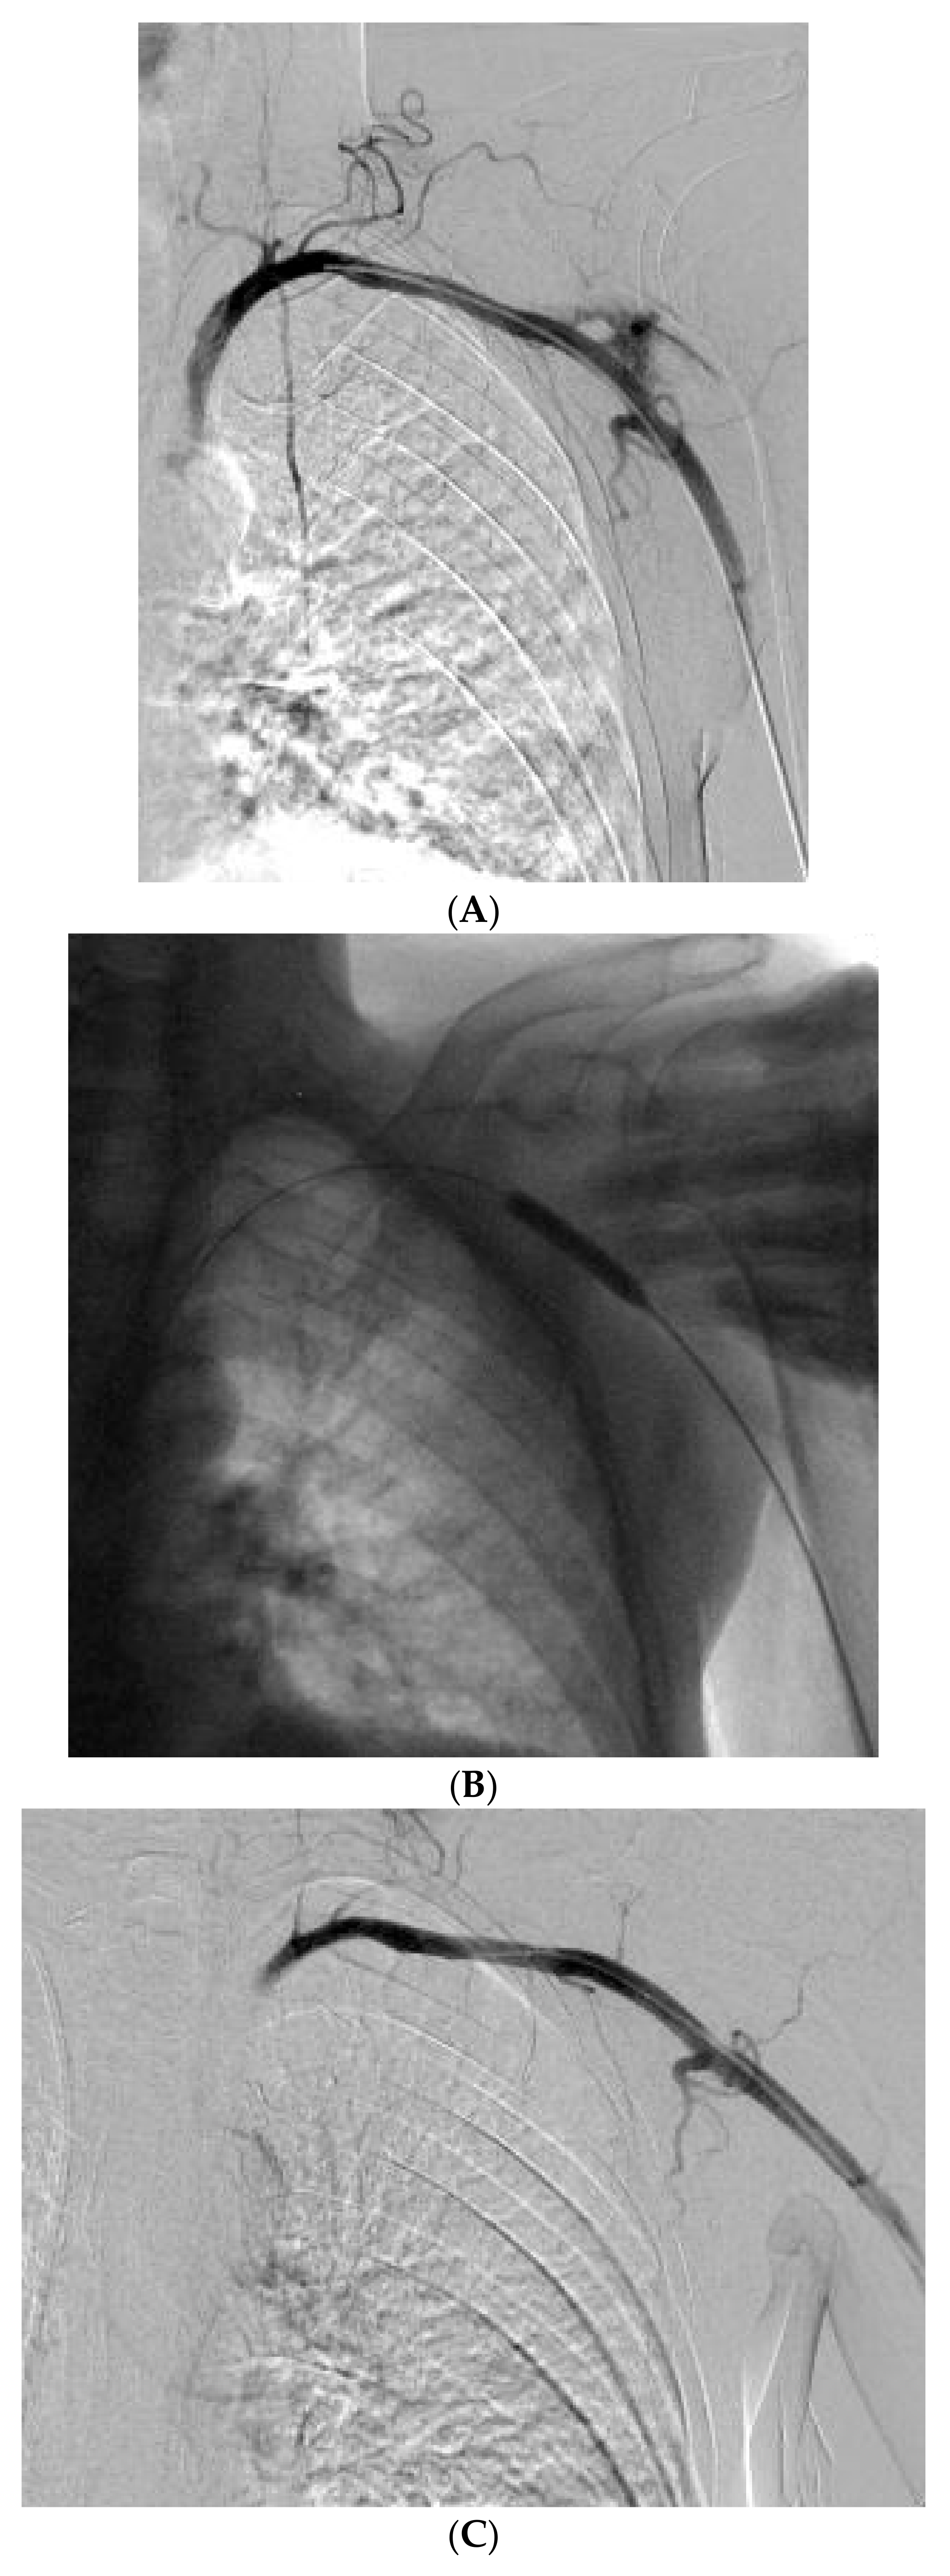

After initial patient stabilization, emergency CT angiography (Figure 2A) confirmed that the catheter had been inserted into the right common carotid artery. Vascular surgeons and interventional radiologists were consulted and external pressure application was decided as the preferred method for safe catheter removal. Alternatively, upon plan failure, internal intravascular balloon tamponade was to be used concurrently with external pressure application. The patient was transported to the Interventional Radiology Unit (Figure 2B), where a 5F sheath and catheter were inserted through the right brachial artery. The patient reported bradycardia at approximately 45–50 bpm that was noted upon patient admission to the ICU and an isoproterenol infusion was initiated and titrated to approximately 65 bpm. The patient was additionally monitored with bilateral cerebral oximetry monitoring. The catheter was slowly removed and firm external pressure was applied to the site of entry for 15 min. No significant changes were observed to the patient’s cerebral oximetry throughout the procedure. Subsequent angiography revealed no leaks or fistulae (Figure 2C). No further complications from the accidental intra-arterial catheter insertion were noted and no abnormal neurological findings were noted upon the patient’s awakening trial on his 4th and 5th day of admission.

Figure 2. (A) Digital angiography confirming right common carotid artery (CCA) catheterization with a CVC (white arrow). An angiography catheter in the arterial system is also visible (black arrow). (B) Angiography during removal of the CVC and compression of the CCA. (C) Final result after release of compression, 5 min later with no evidence of extravasation.